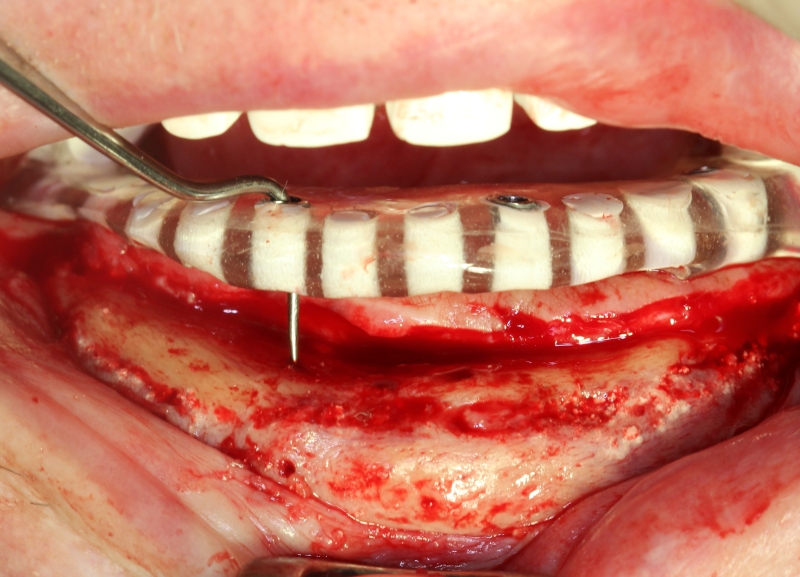

11/14 - Surgical guide in situ

Block augmentation with maxresorb®, collprotect® membrane & autologous bone blocks - Prof. Dr. Dr. D. Rothamel